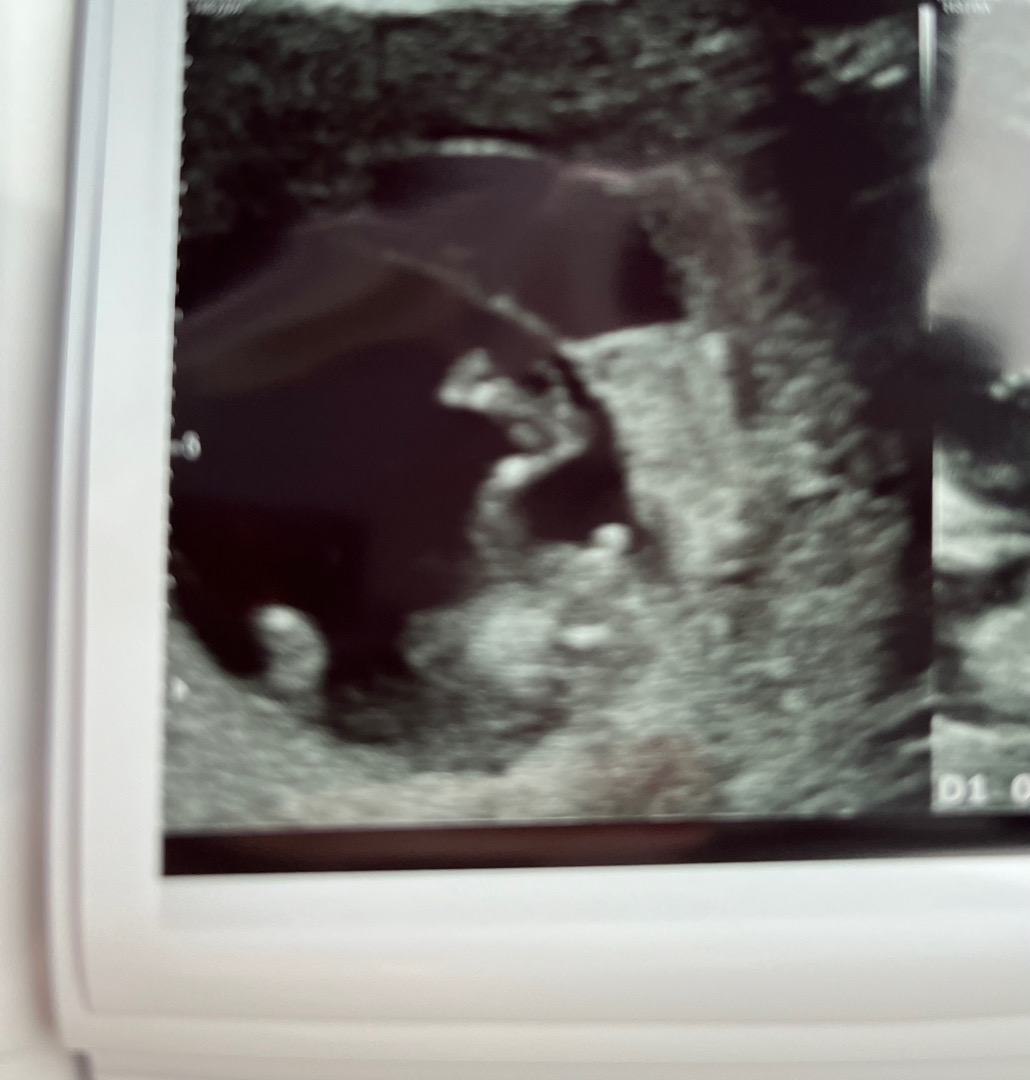

11주4일 초음파 보고 왔어요~ 각도법 봐주세요!!

저 가운데 톡 튀어 나온게 딸일까요 아들일까용?? 맘님들 알려주세요!! 저 기다란건 다리예요!